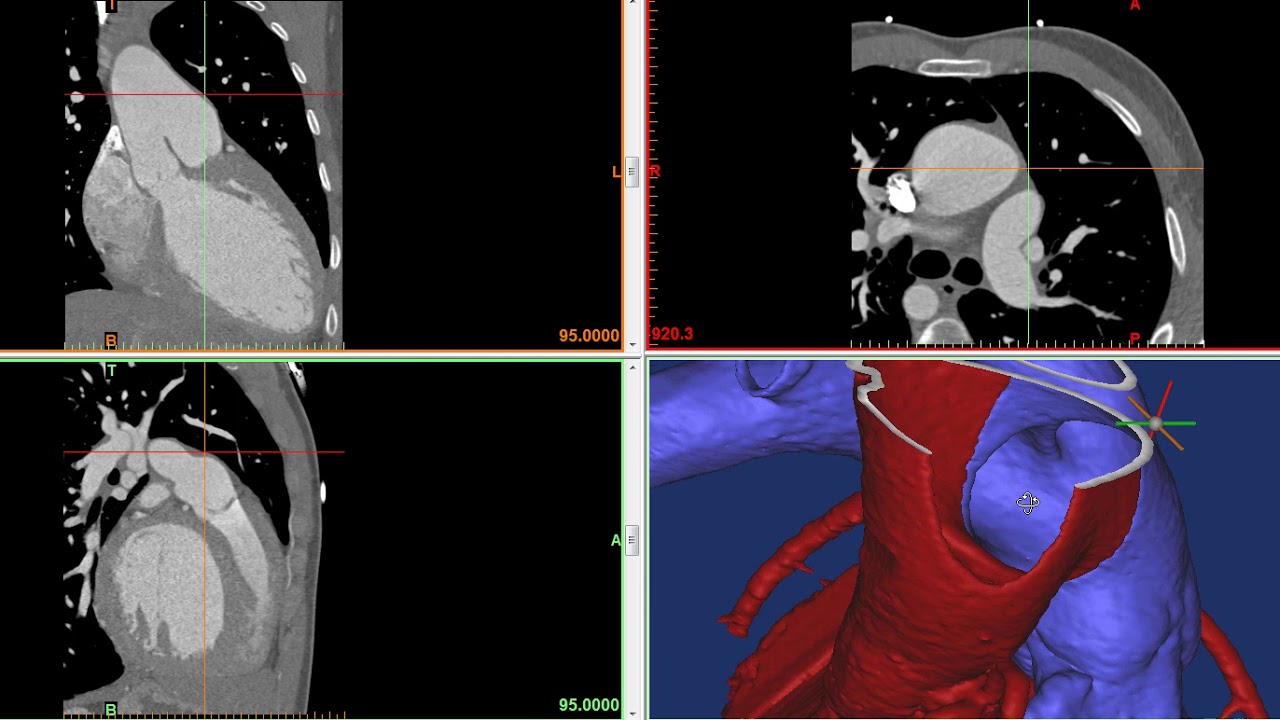

Aortopulmonary window YouTube Air Pocket Near Heart In rare cases, air may enter the area between. Air from the mediastinum can move under the skin of the chest, face, or neck. Most pneumomediastinum requires no treatment, with the air being gradually absorbed on the following days. It’s when air gets into the upper chest and starts accumulating, usually due to trauma or other illnesses that cause air. Air Pocket Near Heart.